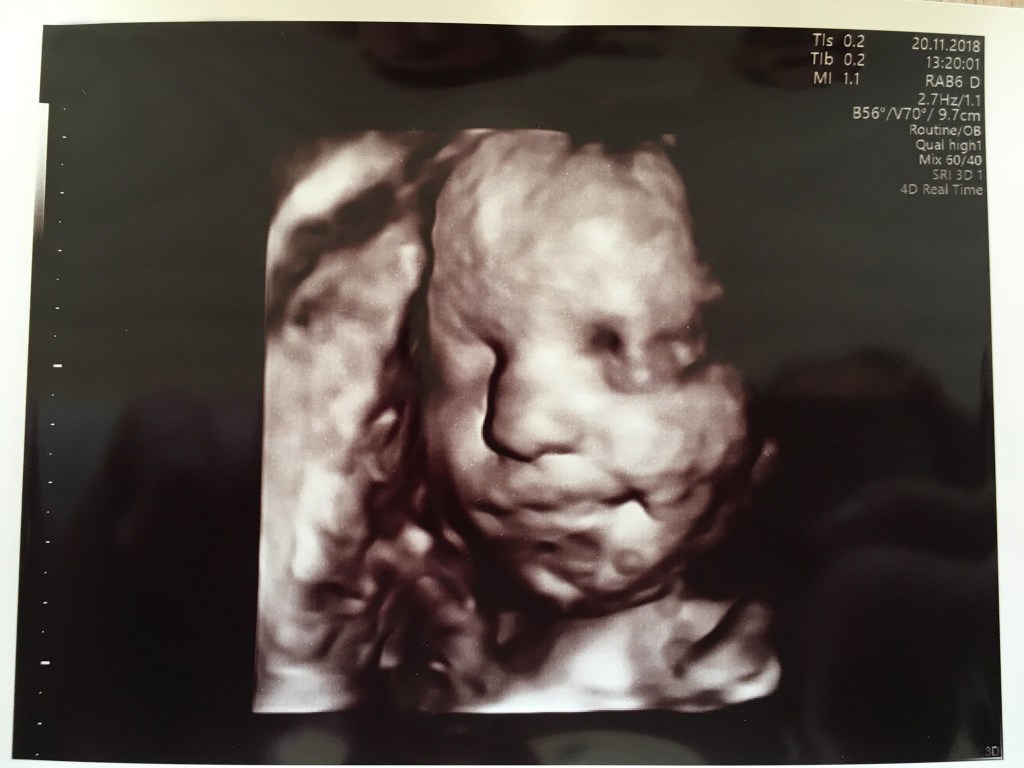

Selvom det var første gang jeg nogensinde skulle have en ultralydsscanning og se et barn i min mave, føltes det som det mest naturlige i verden. Jeg lagde mig til rette på briksen, trak lidt ned i mine cowboybukser og Martin satte sig i den store lænestol ved siden af og tog min hånd. For enden af briksen var en stor skærm, hvor vi kunne følge med i scanningen. Hun advarede mig om det kolde gele og smurte min mave forsigtigt ind, inden hun satte scanneren på. Og lige dér lå vores lille vidunder. Den lillebitte baby lå på siden med ryggen mod os, så vi kunne se den søde numse og de små ben, som han havde trukket op under sig. (På det tidspunkt vidste vi selvfølgelig intet om at det var en lille dreng der lå derinde og moonede til os).

I 10 minutter holdt vi i hånden og kiggede bare på en kidneybønne, der boblede rundt. En kidneybønne, der dengang var 9+4 uger gammel. Da vi var færdige tørrede hun geléen af min mave med et lille varmt håndklæde. Hun trykkede os begge i hånden og sagde tillykke med vores fine lille baby, før hun forlod rummet og gav os god tid til at samle vores ting.

Dagen efter scanningen kom vores forældre og søskende forbi til middag. Jeg var simpelthen så spændt på at fortælle dem, at der var en lille Blob inde i min mave. I to små æsker havde vi lagt et scanningsbillede, som vi fik med fra privatklinikken i Gothersgade. Æskerne blev overrakt til vores mødre, som jeg helt ærligt ikke tror havde fattet nogen form for mistanke forinden. Utroligt nok. Der blev helt stille omkring bordet, mens de synkront forsigtigt åbnede æskerne. Jeg sad overfor min mor og fulgte med i hvordan hendes øjne pludseligt blev lige så store som tekopper, ligesom hendes mund. Hun kiggede på mig og sagde “Er det rigtigt?!” og nærmest grinede af overraskelse. Min svigerfar som sad i den anden ende af bordet mumlede noget i retning af “Det havde jeg da regnet ud for længst”.. Okay, så siger vi det, du gamle (;